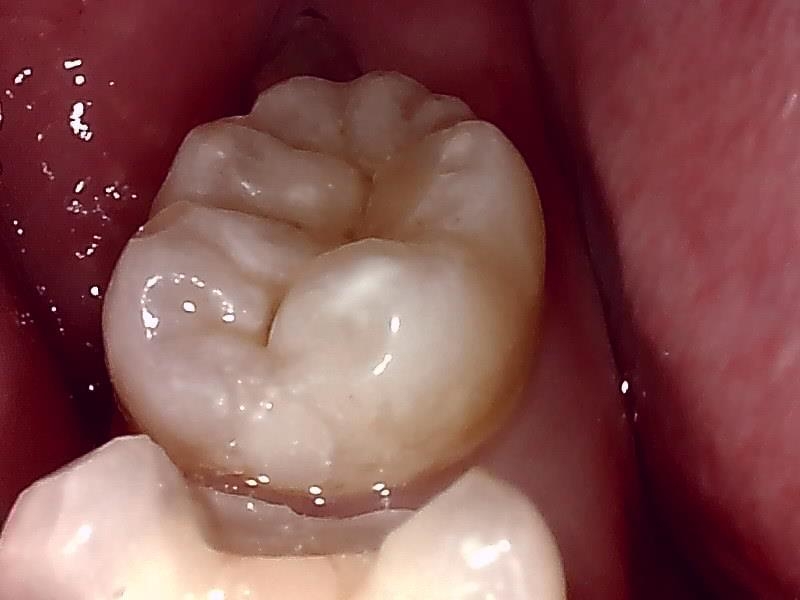

術前の咬合面の写真